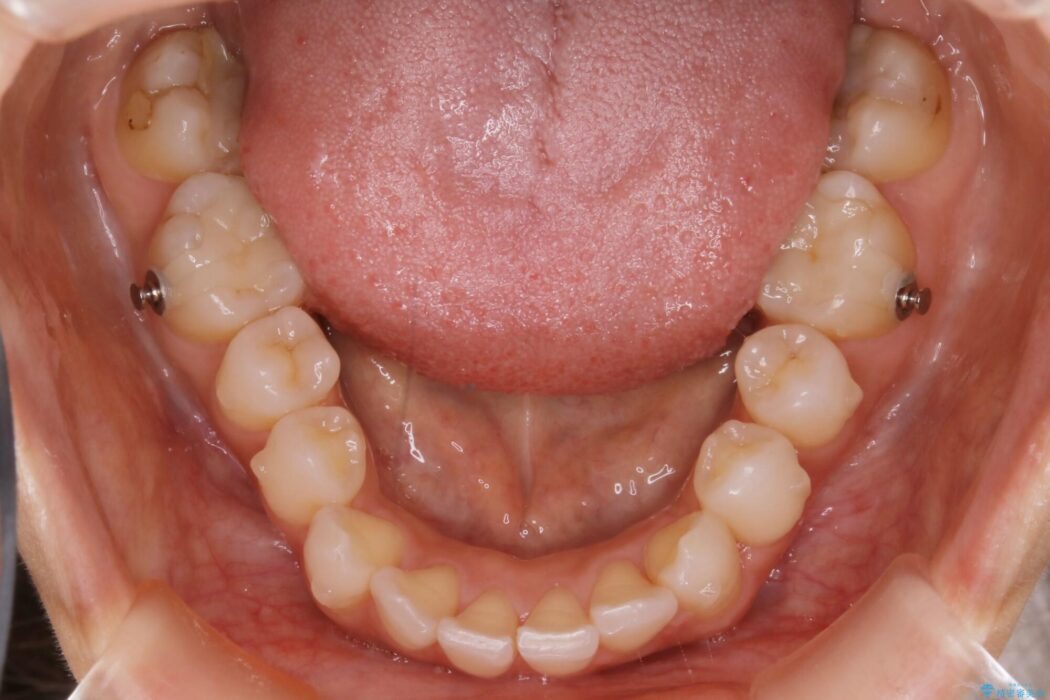

軽度のガタつきと不正咬合が見受けられましたので、インビザラインでの矯正治療を計画しました。

また確認したところ前歯と奥歯にセラミッククラウンで治療した歯があったため、そちらに影響のない範囲内で口腔内全体の噛み合わせが改善されるように歯を動かしていくことになりました。

本症例ではセラミッククラウンのかぶせ物をした歯が複数ありました。

セラミック等の被せ物がある場合、それ自体の外形は矯正治療では変えられないため天然歯の移動に影響を与えてしまうことがあります。

加えてインビザラインでの治療上設定されるアタッチメント(歯の表面に付けるプラスチックの突起)が外れやすい場合が多く、歯の移動に対する力が不足する可能性があります。